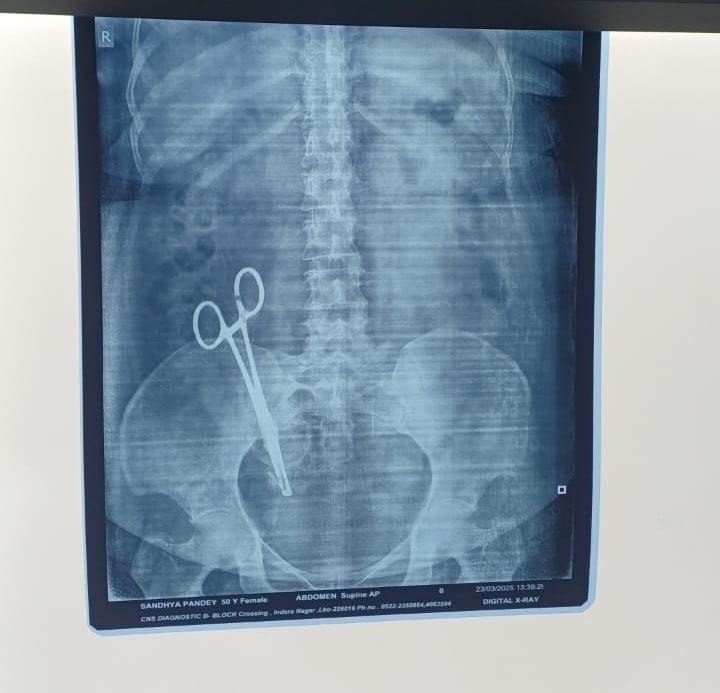

लखनऊ. श्री मेडिकल केयर, इंदिरानगर में 17 साल पहले एक सीजेरियन डिलीवरी हुई थी. ऑपरेशन के दौरान महिला के पेट में कैंची छूट गई. इसका खुलासा 17 साल बाद हुआ. जब महिला का एक्स-रे (X-ray) निकाला गया. रिपोर्ट देख डॉक्टर्स के भी होश उड़ गए. वे भी एक्स-रे देखकर हैरान रह गए. इस मामले में महिला के पति अरविंद पांडेय ने गाजीपुर पुलिस में तहरीर दी है.

तहरीर के मुताबिक 26 फरवरी 2008 को महिला को प्रसव पीड़ा हुई. जिसके बाद उसे इंदिरानगर के एक नर्सिंग होम में भर्ती कराया गया था. वहां सीजेरियन ऑपरेशन के जरिए एक बच्चे का जन्म हुआ, लेकिन ऑपरेशन के दौरान डॉक्टरों की लापरवाही से कैंची पेट में ही छूट गई. इसके बाद से महिला को पेट दर्द की शिकायत होने लगी. कई डॉक्टरों को दिखाने और इलाज के बाद भी हालत में कोई सुधार नहीं हुआ.

हाल ही में महिला ने एक्स-रे कराया. जिसमें इसका खुलासा हुआ. जिसके बाद महिला को केजीएमयू (KGMU) में भर्ती कराया गया. यहां 26 मार्च को सर्जरी के बाद डॉक्टरों ने कैंची निकाल दी. मामले में अरविंद कुमार का इंदिरानगर में डॉक्टर पुष्पा जायसवाल पर आरोप है कि इस लापरवाही के कारण उनकी पत्नी को 17 साल तक शारीरिक और मानसिक कष्ट झेलना पड़ा.